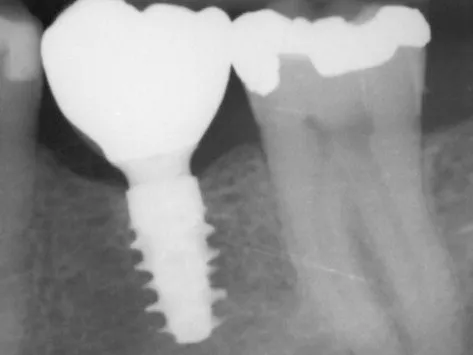

Straumann® BLX is the winning combination of innovative design and surface technology with high-performance material designed for predictable results. Dr. Eirik Aasland Salvesen from Oris Dental in Stavanger, Norway, and executive director of the Oris Academy, was the responsible surgeon of the first Straumann® BLX in human case.